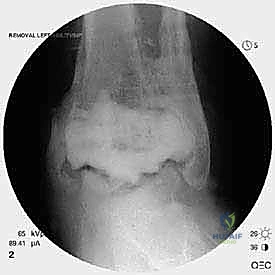

مراجعة مفصل الكاحل الصناعي (Agility) وعلاج كسور الكعب: دليل شامل للمرضى

مراجعة مفصل الكاحل الصناعي هي إجراء جراحي ضروري لمعالجة المشاكل التي قد تنشأ بعد الجراحة الأولية، مثل كسور الكعبين أو عدم استقرار المفصل. يتضمن العلاج التشخيص الدقيق عبر الأشعة السينية والتصوير المقطعي، يليه التدخل الجراحي لتثبيت الكسور واستعادة وظيفة الكاحل، مع التركيز على التعافي المبكر.

تُعد جراحة مراجعة مفصل الكاحل الصناعي (Revision Total Ankle Replacement) من الإجراءات الجراحية المتقدمة والبالغة الدقة في عالم جراحة العظام الحديثة. لا تقتصر هذه الجراحة على مجرد استبدال مفصل تالف بآخر جديد، بل هي عملية إنقاذ معقدة للغاية تهدف إلى معالجة المشاكل الميكانيكية والبيولوجية التي تنشأ بعد الجراحة الأولية. من أبرز هذه المشاكل: الفشل الميكانيكي للمفصل، تحلل العظام (Osteolysis)، أو حدوث كسور معقدة في الكعبين (Malleolar Fractures) المحيطة بالمفصل الصناعي. يتطلب هذا الإجراء تقييماً سريرياً وشعاعياً دقيقاً يشمل التصوير المقطعي ثلاثي الأبعاد والأشعة السينية، يليه تدخل جراحي دقيق لاستعادة التوازن الحيوي والميكانيكي للكاحل والحفاظ على الطرف من البتر أو الدمج.

إن نظام (Agility) لمفصل الكاحل كان يُعد في وقت من الأوقات ثورة في عالم جراحة العظام، حيث اعتمد تصميمه على دمج المفصل الليفي الظنبوبي الشظوي (Syndesmosis) لتوفير قاعدة عريضة وثابتة للمفصل الصناعي. ومع ذلك، بمرور السنوات، أظهرت الدراسات والمتابعات السريرية أن بعض المرضى يعانون من مضاعفات مثل عدم التئام هذا الدمج، أو هبوط المفصل (Subsidence)، أو تكون أكياس عظمية تؤدي إلى تخلخل الزرعة.

- الأشعة السينية مع تحميل الوزن (Weight-bearing X-rays): لتقييم الزوايا الميكانيكية وتحديد مدى هبوط المفصل أو وجود كسور في الكعب.